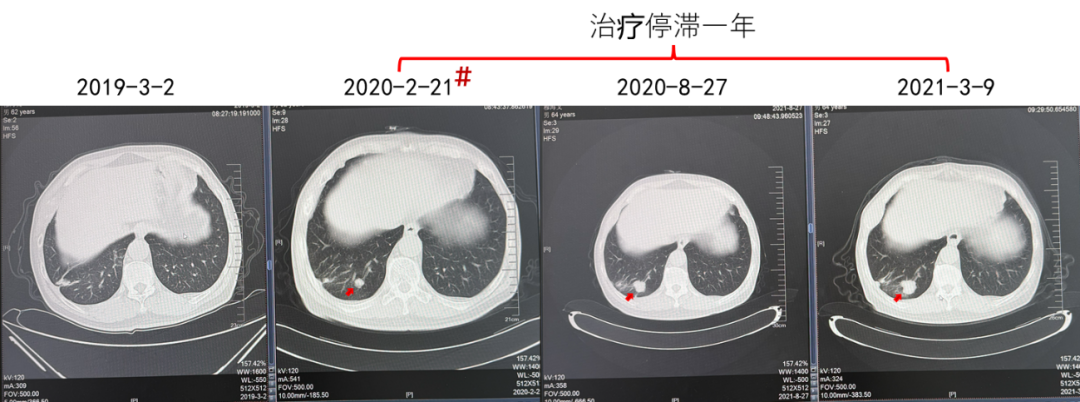

疗效:肋骨病灶疾病稳定(2年),肺部病灶部分缓解(2年)。

(治疗停滞1年,患者对侧肾上腺肿瘤发生进展)